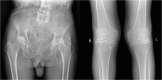

Alkaptonuria

Keywords: Alkaptonuria; Homogentisic acid; Ochronosis.